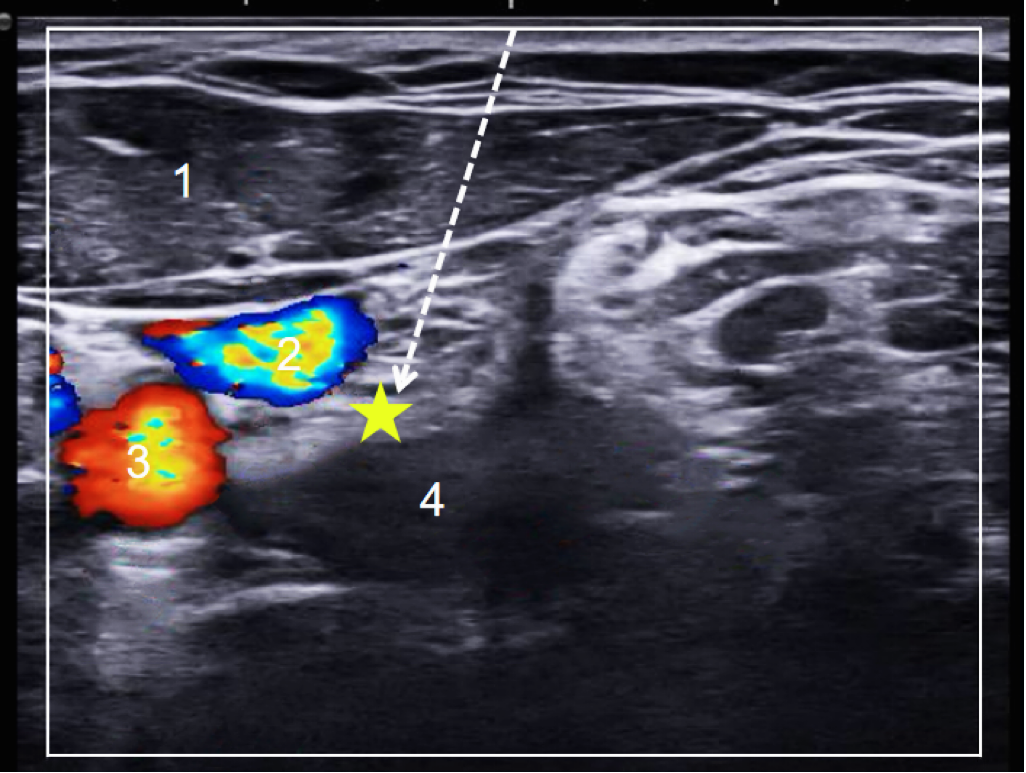

图7:超声引导下星状神经节阻滞治疗

图8 超声引导下星状神经节阻滞穿刺路径

注:1为胸锁乳突肌,2为颈内静脉,3为颈总动脉,4为颈长肌,

⭐为星状神经节阻滞定位点,虚线箭头为平面外穿刺路径